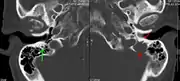

The diagnostic examination of a person with suspected multiple myeloma typically includes a skeletal survey. This is a series of X-rays of the skull, axial skeleton, and proximal long bones. Myeloma activity sometimes appears as "lytic lesions" (with local disappearance of normal bone due to resorption) or as "punched-out lesions" on the skull X-ray ("raindrop skull"). Lesions may also be sclerotic, which is seen as radiodense.[70] Overall, the radiodensity of myeloma is between −30 and 120 Hounsfield units (HU).[71] Magnetic resonance imaging is more sensitive than simple X-rays in the detection of lytic lesions, and may supersede a skeletal survey, especially when vertebral disease is suspected. Occasionally, a CT scan is performed to measure the size of soft-tissue plasmacytomas. Bone scans are typically not of any additional value in the workup of people with myeloma (no new bone formation; lytic lesions not well visualized on bone scan).

A CT of the brain revealed a lytic lesion in the left temporal bone (right side of image), and petrous temporal bones involving the mastoid segment of the facial nerve canal. Red arrows: lesion; green arrow: normal contralateral facial nerve canal. The lesions are consistent with a myeloma deposit.